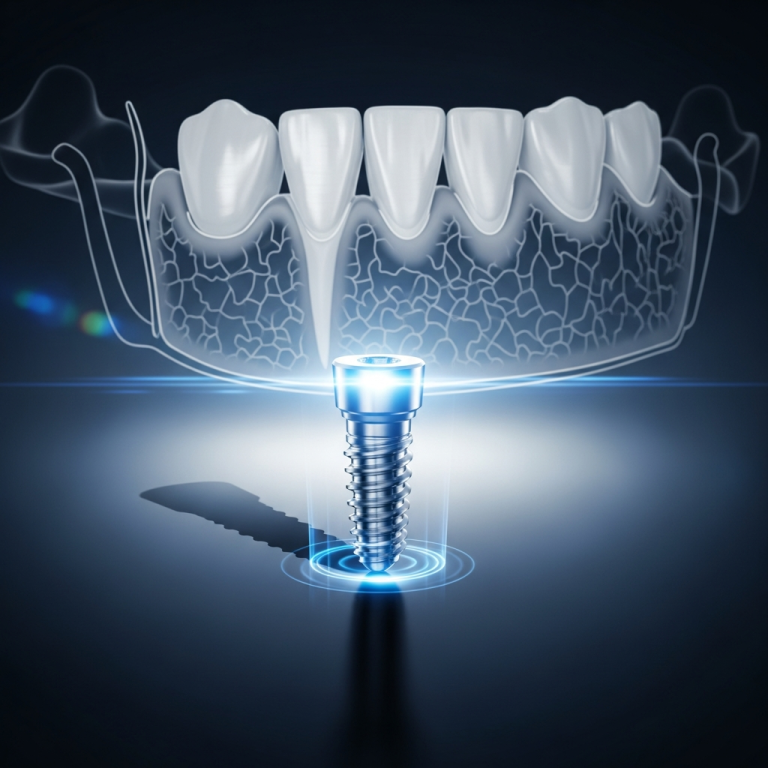

- Design specific: Aceste implanturi sunt adesea monobloc (dintr-o singură piesă), cu o suprafață netedă și filetări laterale, menite să angajeze straturile de os cortical cu densitate mare (osul bazal).

- Ancorare mecanică: Stabilitatea primară nu depinde majoritar de osteointegrarea în osul spongios, ci de blocajul mecanic ferm în două sau mai multe plăci corticale, de unde și denumirea de „bicortical”.

Mecanismul de Stabilitate

Stabilitatea implanturilor bicorticale se bazează pe principiul osteofixării prin inserarea lor în osul cortical rezistent, adesea la nivelul maxilarului superior și inferior. Această fixare robustă minimizează micromișcările și permite transferul forțelor masticatorii direct către structurile osoase dense, contribuind la o predicție bună a succesului pe termen lung, chiar și sub încărcare funcțională precoce.